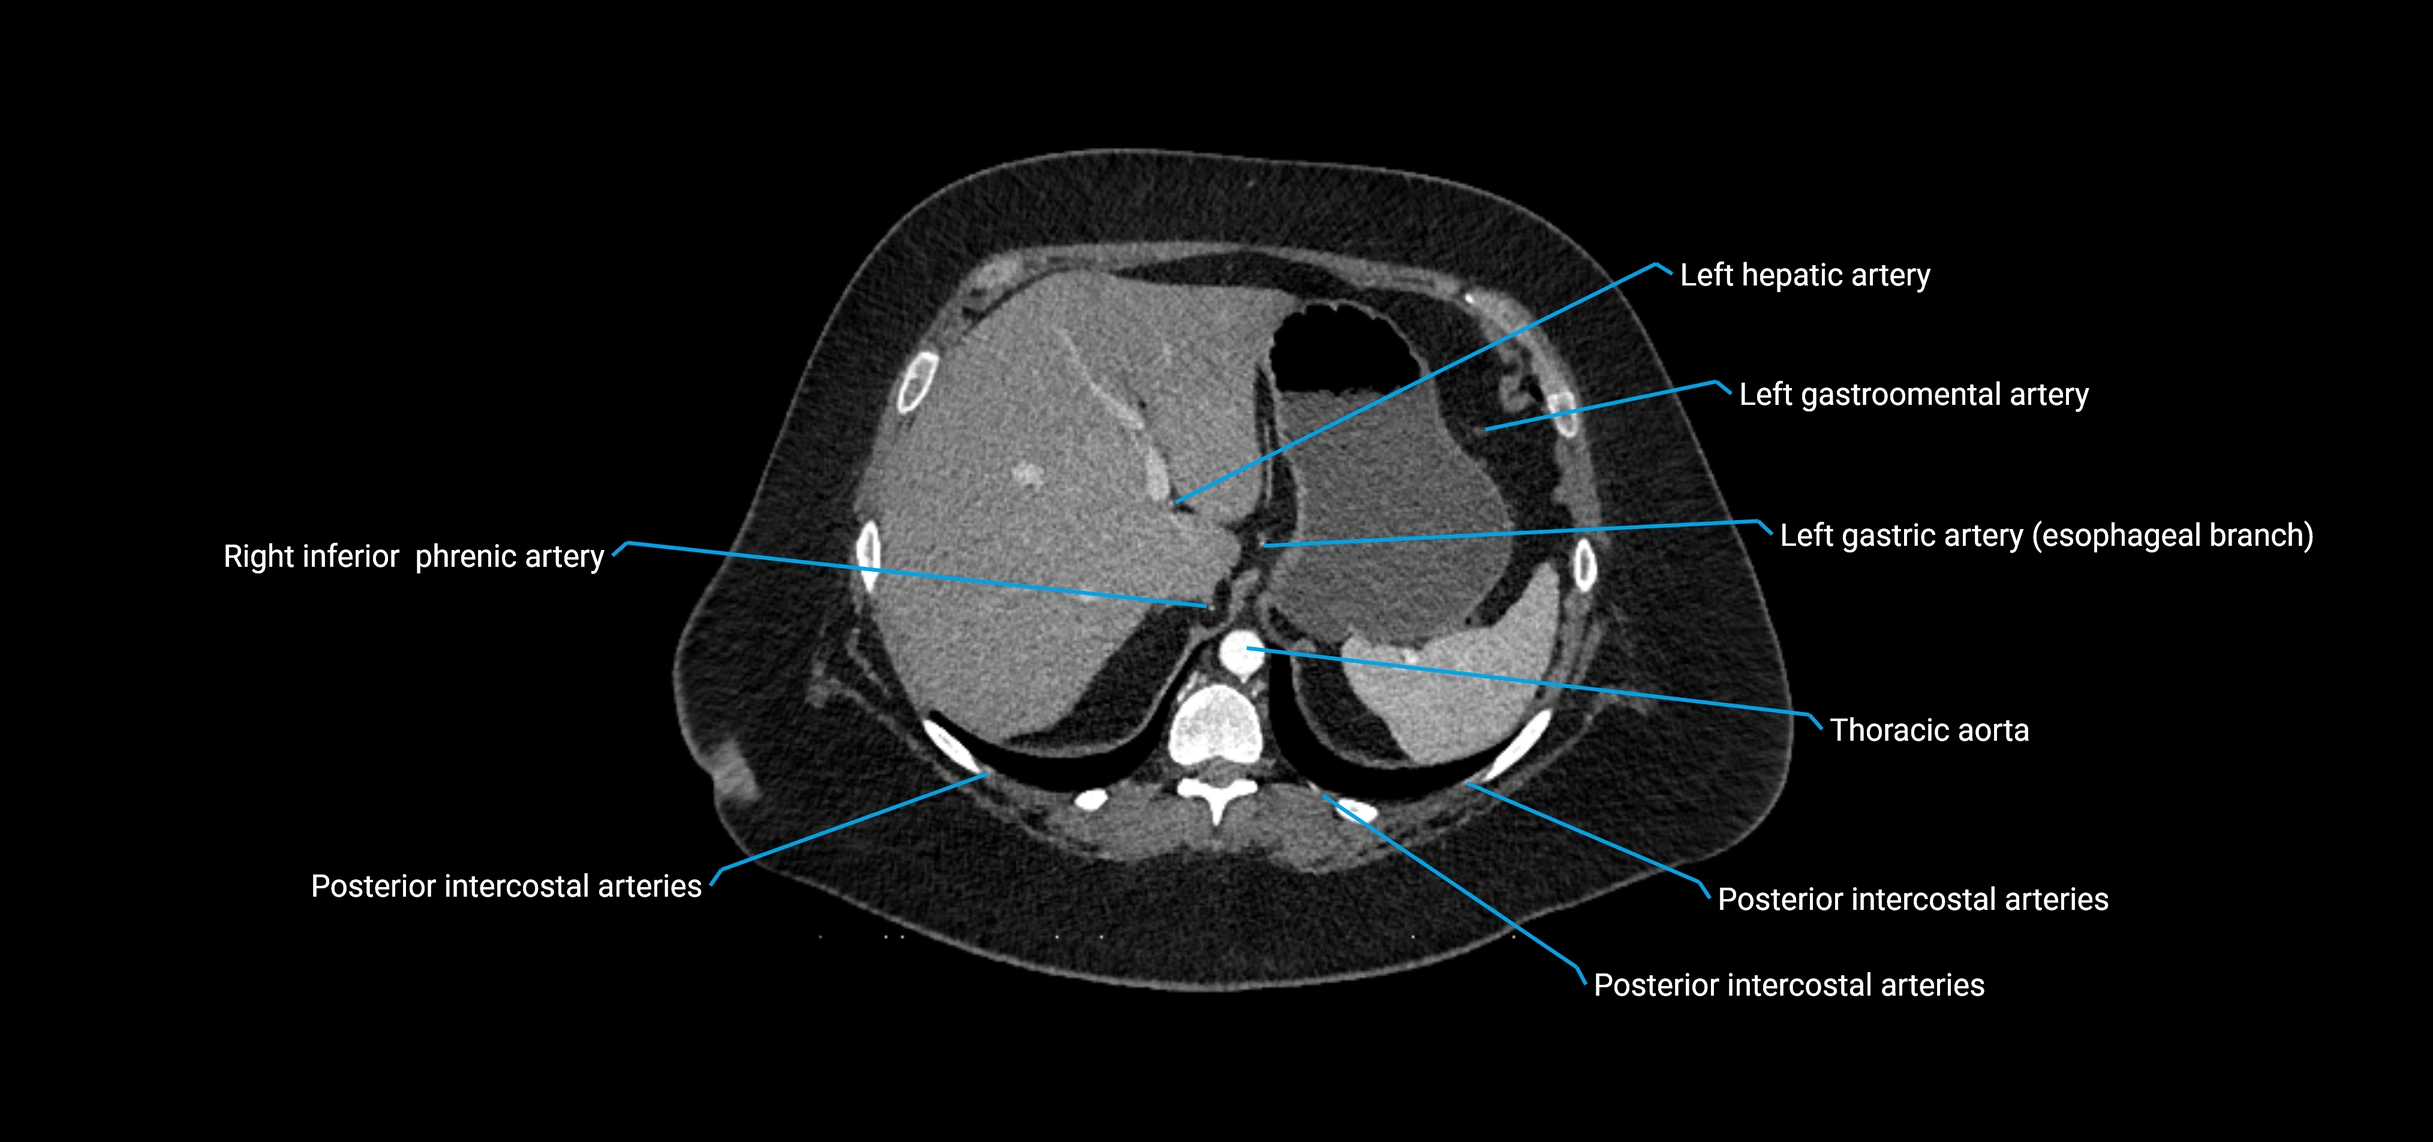

• Unpaired visceral branches: celiac trunk, superior mesenteric artery (SMA), inferior mesenteric artery (IMA)

• Paired visceral branches: middle suprarenal arteries, renal arteries, gonadal arteries (testicular or ovarian)

• Parietal branches: inferior phrenic arteries, lumbar arteries, median sacral artery

Contrast-enhanced CT (CTA):

• Gold standard for abdominal aortic imaging

• Provides excellent detail of lumen, wall, aneurysm, thrombus, and branch vessels

• Multiplanar and 3D reconstructions help in aneurysm measurement, stent graft planning, and dissection evaluation

• Detects acute rupture, traumatic injury, or occlusion with high sensitivity